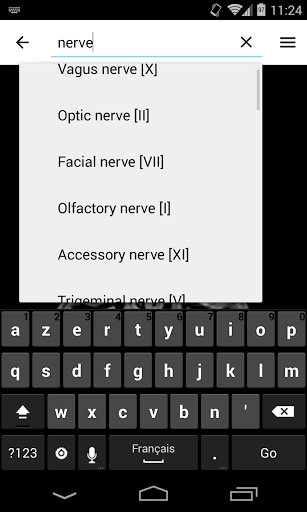

- Localice fácilmente las estructuras anatómicas gracias a la búsqueda de índice

*Encuentre sus partes anatómicas más fácilmente gracias a la nueva función de búsqueda, más intuitiva y poderosa.